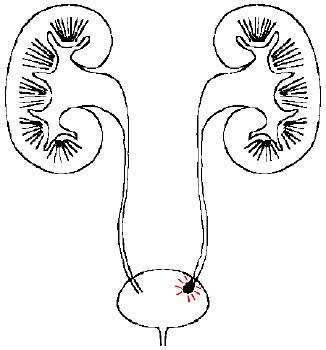

泌尿系结石就是在人体的肾脏、输尿管、膀胱等部位形成的以碳酸钙、草酸钙、尿酸、磷酸钙、磷酸镁等为主要成分的结晶体形成的异物,导致泌尿系统尿液排泄障碍的一种梗阻性疾病,包括肾结石、输尿管结石、膀胱结石,统称泌尿系结石。

昨晚上夜班来了一个急腹症的男病人,36岁,说是近半个月来出现尿液发红,时有时无,特别是活动后最容易出现左侧肾区疼痛,当时也没有重视进一步检查,这不突然出现左侧肾区剧烈疼痛,像撕裂一样,还向会阴部放射,疼得浑身出汗,忍受不了才来医院看看,经检查是:双侧肾盂结石,左侧输尿管结石梗阻,左侧肾积水,当时邀请碎石科给予急诊碎石治疗后,疼痛缓解了,复查泌尿系彩超提示:左侧输尿管结石梗阻解除。相信大家对结石都有所耳闻,今天就来说说导致尿液发红的泌尿系结石,您可要注意了。